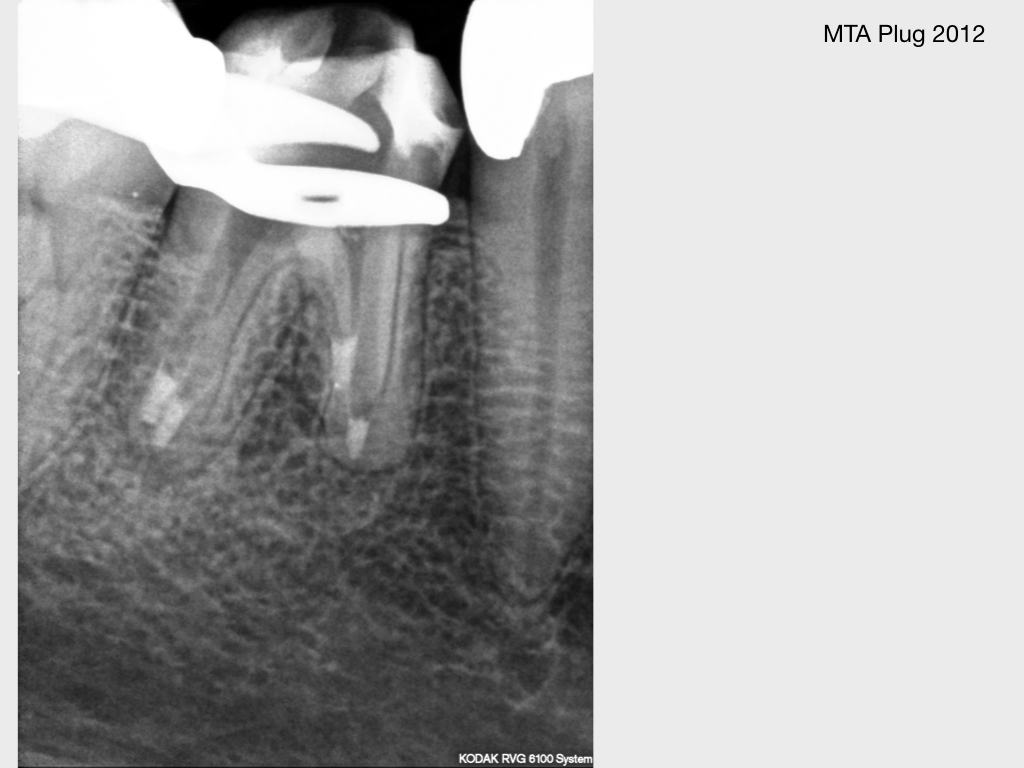

Kurz berichtet – Z.n. WSR